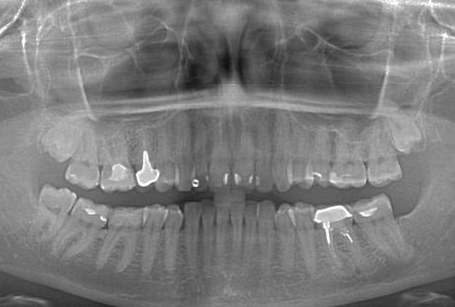

Перед имплантацией зубов необходимо получение панорамного снимка челюстей.

Такая необходимость связана с определением местоположения нижнечелюстного канала, толщины дна гайморовой пазухи и других анатомических образований.